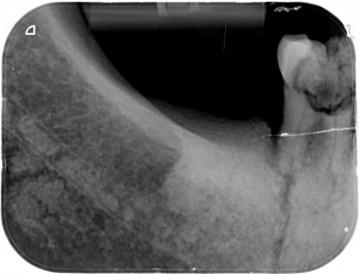

Tanden op kaakdeel (Rechts)   M3 derde kies (verstandskies ontbreekt )  M2 tweede grote kies. M1 eerste grote kies..

P2 tweede kleine kies .P1 eerste kleine kies . een hoektand , twee snijtanden .